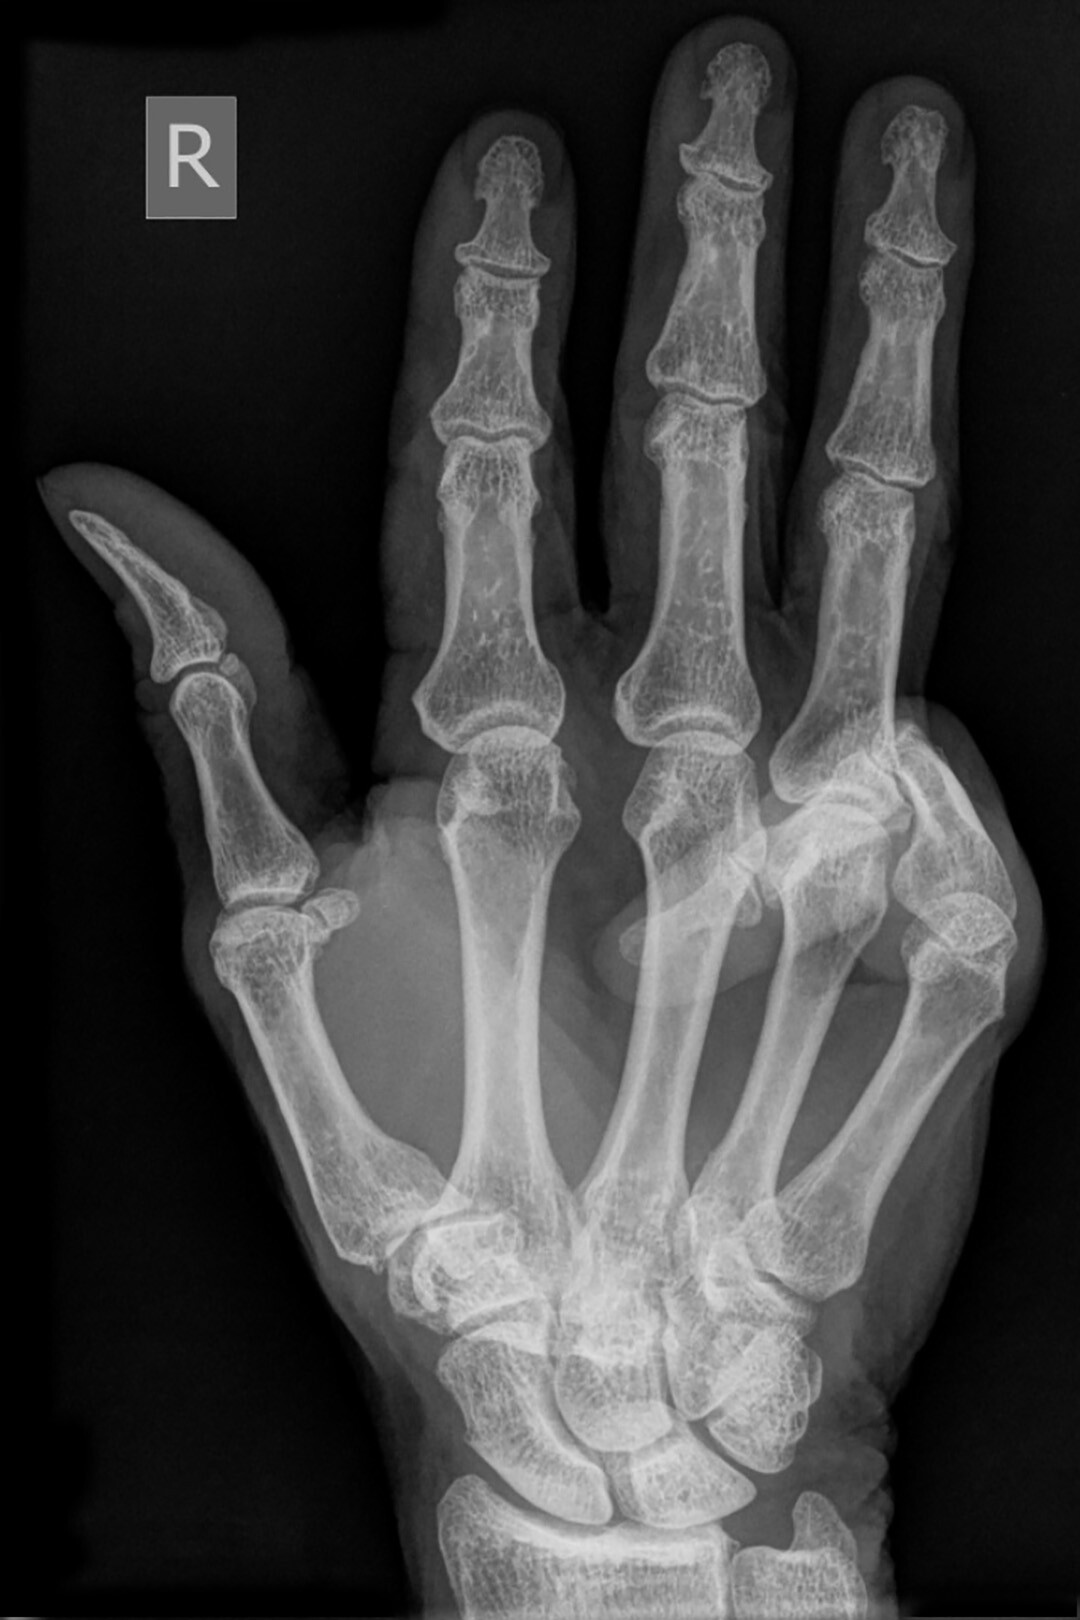

Is Dupuytren Contracture Reversible . dupuytren contracture is a condition that causes one or more fingers to bend toward the palm of the hand. Dupuytren’s disease, also called dupuytren’s contracture, is a. primary outcomes of interest were the following: Range of motion (rom) at the joints, severity of joint contractures,. The proliferative phase has a. dupuytren contracture progresses through three phases: There is no cure, but some limited data suggests that steroid. this surgery is the most invasive option and has the longest recovery time. hand & upper extremityvideos | october 10, 2024. (1) proliferative, (2) involution, and (3) residual. is dupuytren’s contracture reversible?